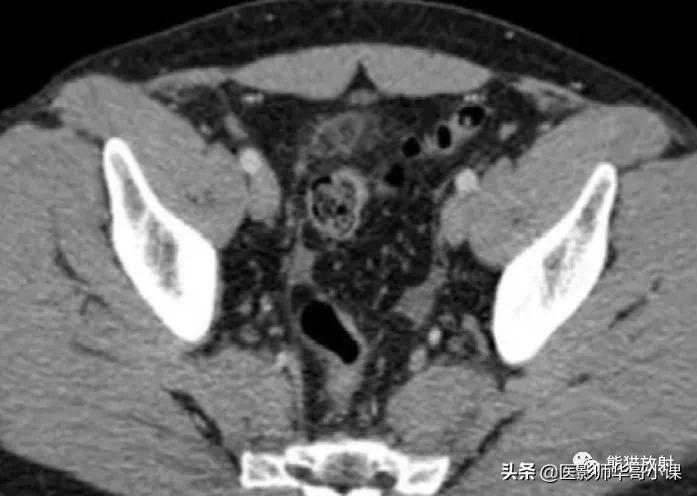

肠脂垂扭转或血栓症可以引起肠脂垂炎。临床表现与急性憩室炎或阑尾炎相似,大多数病例具有自限性。肠脂垂炎的CT表现有助诊断,从而避免不必要的手术。 最常见的CT表现 为直径 小于5cm 的卵圆形脂肪密度病变,与结肠浆膜面毗邻,周围呈炎性改变。肿块周围可见 高密度环形边缘,为炎性的脏层腹膜 (图)。病灶常含有血栓血管造成的高密度中央区。常见邻近结肠壁轻度反应性增厚。

肠脂垂炎。增强CT显示阑尾周围腹膜见一边缘呈高密度的脂肪灶,并周围炎症,位于乙状结肠前方。抗炎治疗后患者的症状减退。